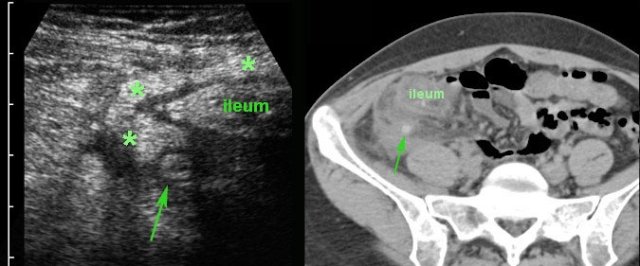

In this patient, US shows large quantities of inflamed fat (*) and the thickened ileum representing successful walling-off of the (imminent) perforation of the appendix (arrow).

Note a calcified fecolith (arrow on CT scan) in the appendix at a higher level.

The longer this process of “walling-off” is going on, the more difficult appendectomy is going to be.

This dilemma is discussed in the chapter “appendiceal mass”.